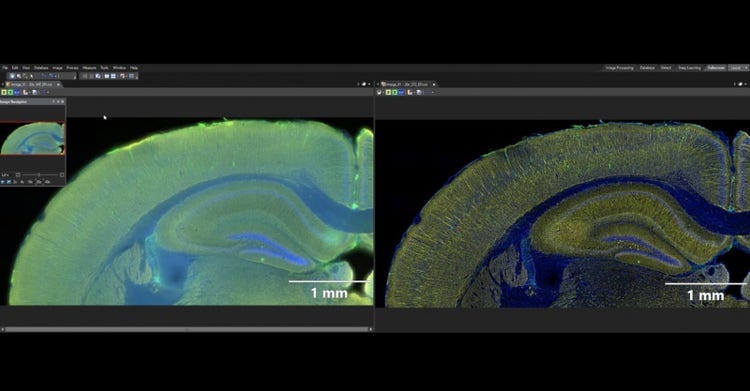

脳研究

AAV-GFPとAAVtdTomatoで標識された皮質視床投射路。

画像データ提供:Hong Wei Dong, MD, PhD, Professor of Neurology, Keck School of Medicine of University of Southern California.